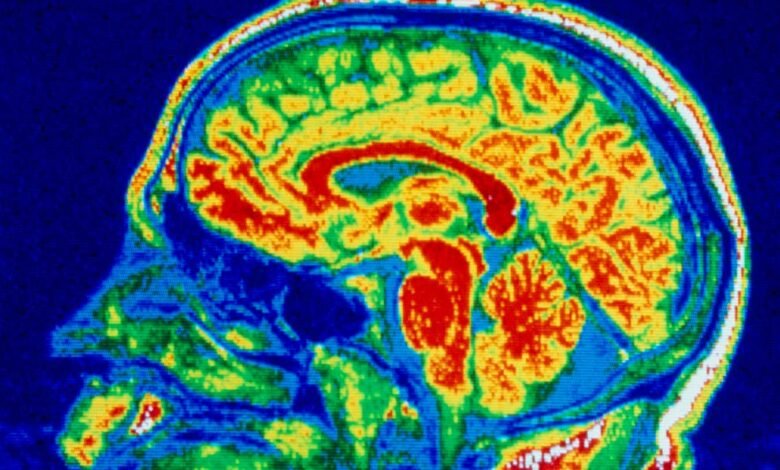

A false-colour nuclear magnetic resonance image of a child’s brain

CNRI/SCIENCE PHOTO LIBRARY